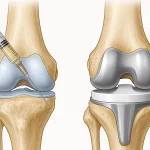

تعویض مفصل زانو چیست؟

تعویض کامل مفصل زانو یا جراحی آرتروپلاستی، یک روش جراحی پیشرفته است که در آن غضروف و استخوان تخریبشده برداشته و با یک مفصل مصنوعی جایگزین میشود. این درمان معمولاً برای بیماران با آرتروز پیشرفته یا درد شدید و غیرقابل کنترل توصیه میشود.

مفصل مصنوعی معمولاً از فلز و پلیاتیلن ساخته میشود و ماندگاری آن بین ۱۵ تا ۲۰ سال است.